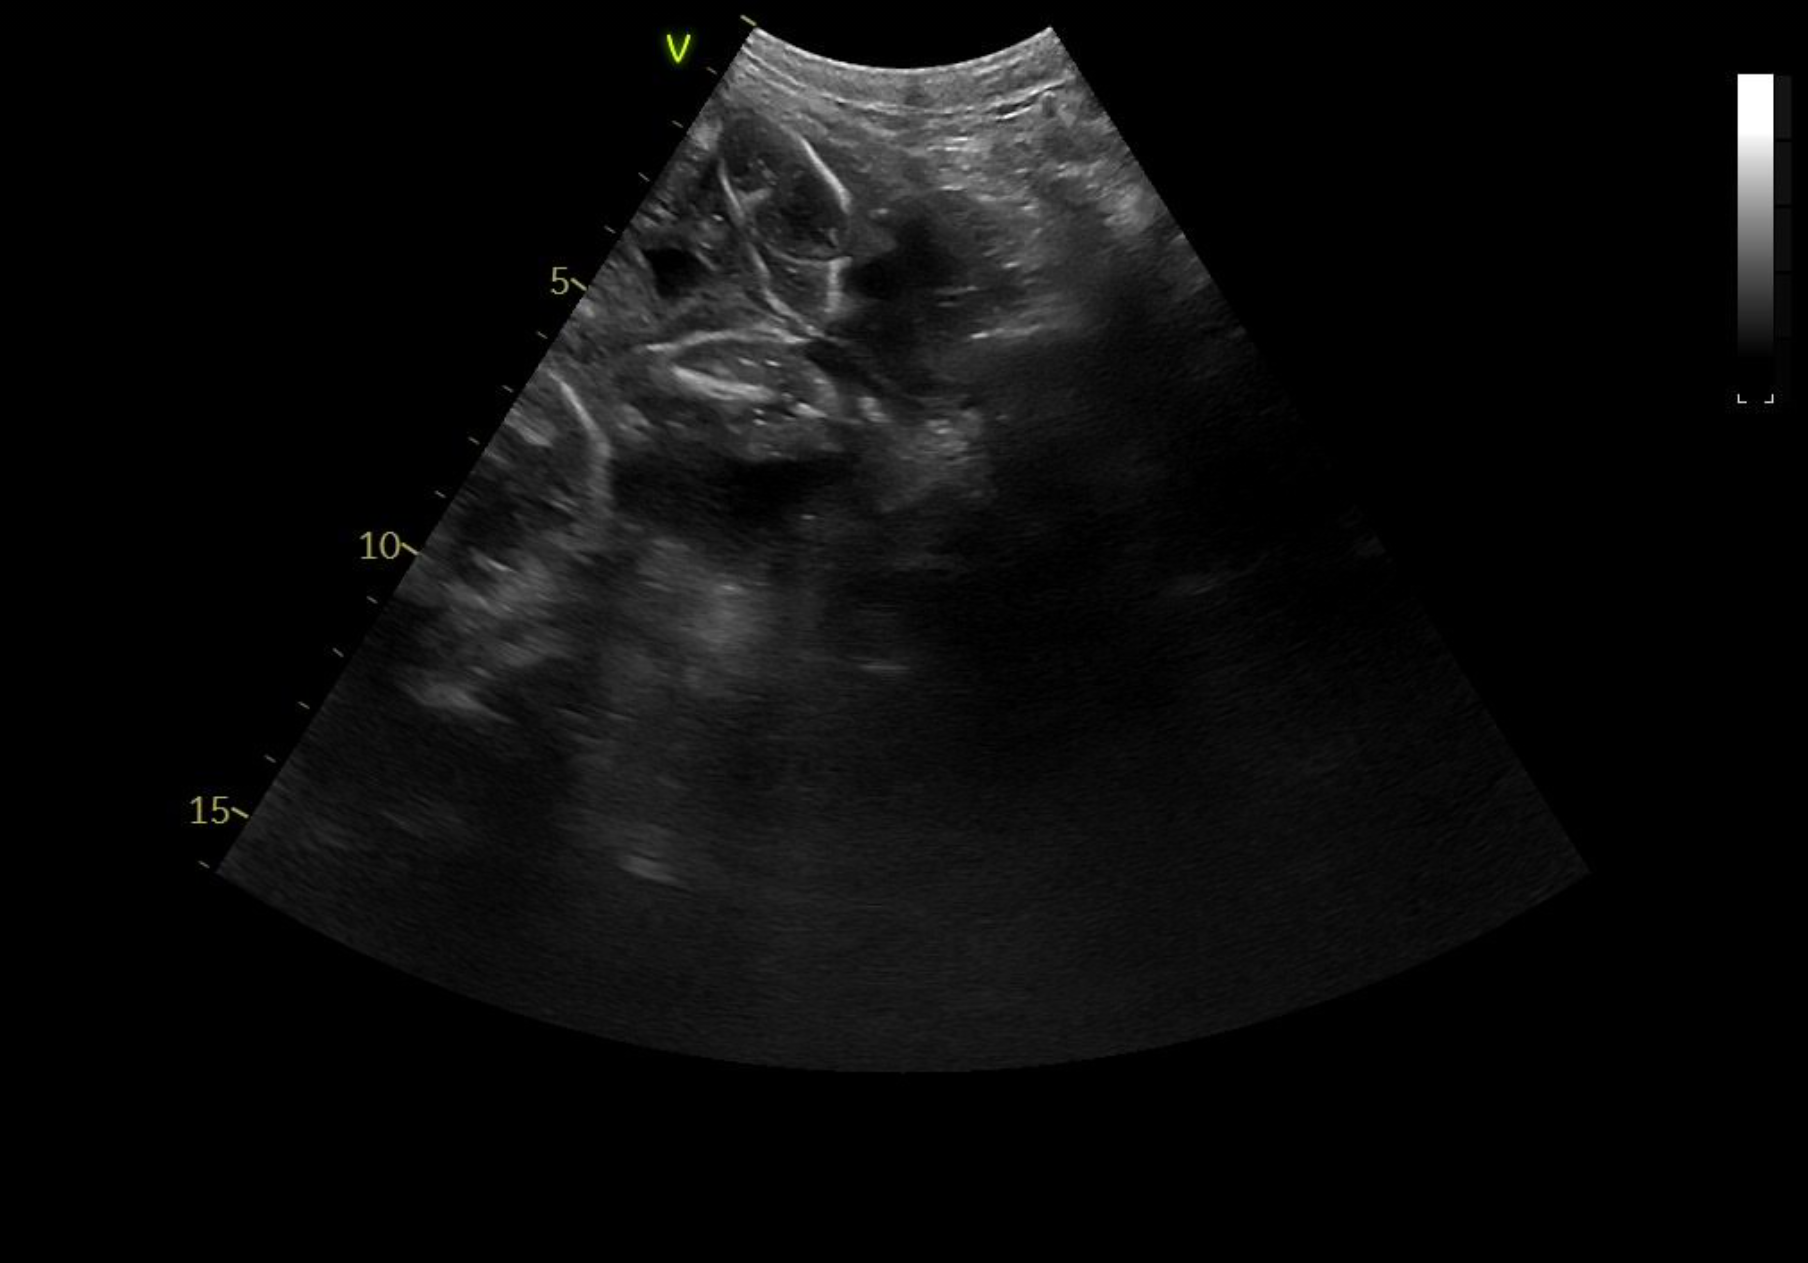

Tessa er scannet igen. Hvalpene er alle i live og har det godt. Deres hoveder er målt til 2 cm.

23.03.2021

Tessa er scannet drægtig. Hvalpene er sunde og er målt til 1,5 cm.